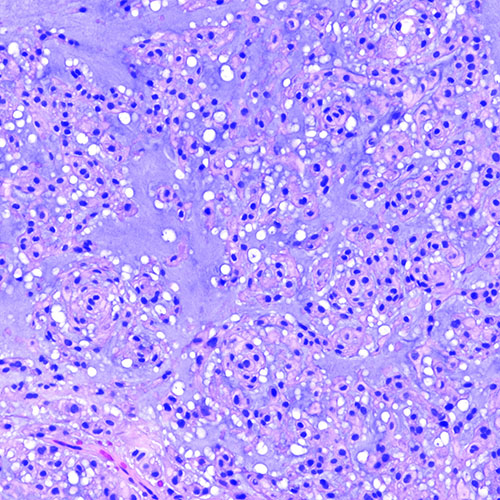

Chordomas occur in one out of one million people. The tumor cells form little bubble-like clusters and often produce a lot of cartilage-like material, seen as blue-grey areas within the tumor. They can form along the spine, invade local structures and even destroy the bones at the base of the skull or the spine. Even after surgical resection and radiation, these tumors usually keep growing back.

Chordoma under a microscope.

Chordoma